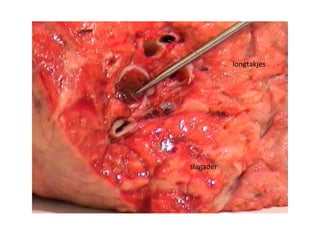

longtakje

ader

slagader

longtakjes